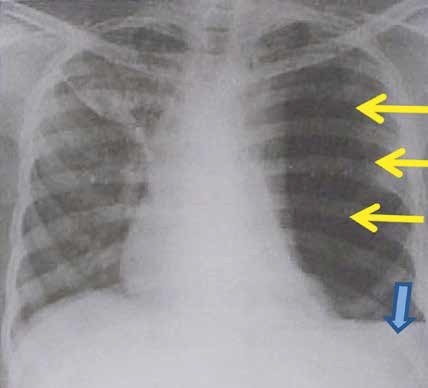

2 – Adolescente masculino de 16 anos de idade, trazido ao pronto-socorro de hospital terciário pelo Serviço de Resgate, foi vítima de queda de bicicleta após colisão em alta velocidade contra anteparo fixo. Paciente relata ter traumatizado a região superior do abdome contra o guidão da bicicleta e refere intensa dor no local. Apresenta ainda trauma craniano, sem perda de consciência, porém refere cefaleia intensa. Nega vômitos. Dados colhidos pela equipe do resgate no local do acidente: Pulso = 112 bpm; pressão arterial = 130 x 90 mmHg; frequência respiratória = 16 irpm; saturação de oxigênio 97% em ar ambiente. Tempo entre acidente e admissão hospitalar: 30 minutos. Na avaliação no pronto- socorro:

A: Vias aéreas pérvias, com colar cervical. B: Murmúrios vesiculares presentes bilateralmente; expansibilidade simétrica; tórax indolor à palpação; sem crepitações; FR = 16 irpm; saturação de O2 98% em ar ambiente. C: Pulso = 108 bpm; pressão arterial = 120 x 70 mmHg; sem sangramento visível. Abdome doloroso à palpação em epigástrio e mesogástrio, onde se evidenciam equimose e escoriação. Toque retal sem alterações, diurese clara. D: Escala de Coma de Glasgow = 15; pupilas isocóricas e fotorreagentes. E: Sem outras alterações. Realizada expansão volêmica com 2.000 ml de soro fisiológico e analgesia. Após essas medidas, o paciente apresenta frequência cardíaca de 86 bpm e pressão arterial de 120 x 70 mmHg. Devido ao traumatismo craniano, associado à cefaleia atual, foi solicitada

tomografia computadorizada de crânio com a imagem apresentada.

Cite a conclusão do laudo desta imagem:

A imagem apresentada no enunciado é de uma Tomografia Computadorizada (TC) de crânio, e disso ninguém duvida. Nesse momento devemos nos fazer uma pergunta óbvia: esse paciente tem indicação

de ser submetido a tal exame? Sim, tem. Embora

esse jovem tenha um Trauma Cranioencefálico (TCE)

leve (Escala de Coma de Glasgow entre 13-15), ele tem indicação de TC, pois apresenta cefaleia intensa. Vamos recordar as principais indicações de TC de crânio no TCE leve: cefaleia intensa, suspeita de fratura aberta de crânio, sinais de fratura de base de crânio, mais de dois episódios de vômito, indivíduos acima de 65 anos, perda da consciência por mais de 5 minutos, amnésia retrógrada por mais de 30 minutos e deficit neurológico focal atribuído ao cérebro.

Voltando a TC do enunciado (FIGURA 1), o que encontramos? Observem uma imagem hiperdensa (branca) entre os sulcos (setas amarelas), uma região

que deveria ser hipodensa (preta), pois é preenchida por liquor. Essa imagem hiperdensa representa sangramento difuso entre os sulcos. Não temos imagem hiperdensa biconvexa, para pensarmos em hematoma epidural, nem imagem hiperdensa que acompanha a convexidade cerebral, para considerarmos o diagnóstico de hematoma subdural. Sendo assim, o nosso diagnóstico é de uma hemorragia subaracnóidea traumática. Alguns candidatos responderam hematoma intraparenquimatoso, mas vejam como a imagem de uma coleção parenquimatosa é bem diferente da apresentada no enunciado (FIGURA 2).